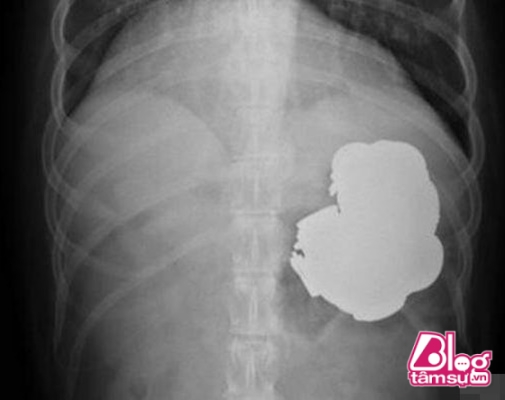

Trong dạ dày của người đàn ông này chứa khoảng 140 đồng tiền vàng, các loại hạt, đinh, vít và những cục pin đã sử dụng.

Ban đầu vì sợ đau nên cả gia đình anh chàng đều phản đối việc bác sĩ sử dụng phương pháp nội soi để kiểm tra vùng dạ dày của anh chàng. Tuy nhiên bác sĩ đã giải thích và dùng phương pháp nội soi không đau, dùng thuốc gây mê để bệnh nhân giảm bớt cảm giác đau đớn và khó chịu. Kết quả của quá trình nội soi khiến các bác sĩ và người nhà bệnh nhân cảm thấy vô cùng sốc khi thấy những thứ nằm bên trong dạ dày của anh chàng. Trong dạ dày của người đàn ông này chứa khoảng 140 đồng tiền vàng, các loại hạt, đinh, vít và những cục pin đã sử dụng.

Các bác sĩ cho biết đây là đều là những loại kim loại cứng, nhọn có thể gây nguy hiểm cho vùng dạ dày của anh chàng. Một vùng dạ dày của người đàn ông đã bị tổn thương bởi đầu nhọn của những chiếc đinh, vít gây ra. Nếu lúc đó không kịp thời đưa anh chàng đi cấp cứu kịp thời anh ta hoàn toàn có thể mất mạng. Nhờ sự nỗ lực của các bác sĩ cuối cùng cũng loại bỏ được tất cả những đống kim loại ra khỏi dạ dày của người đàn ông này. Anh ta đang trong quá trình điều trị phục hồi sau phẫu thuật.